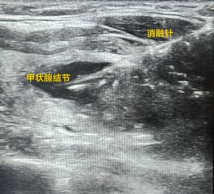

排除手术禁忌后,在彩超引导下穿刺抽取少量液体进行病理化验。当报告确认为良性时,林女士终于放下了长久以来的顾虑。真正的治疗紧随其后:在彩超的清晰“导航”下,一根纤细的消融针被准确送达结节中心。微波能量被激发,针尖迅速升温至120°C,将结节原地“消融”。由于是精准的微创操作,几乎没有出血,颈部只留下一个毫米级的“小针眼”。